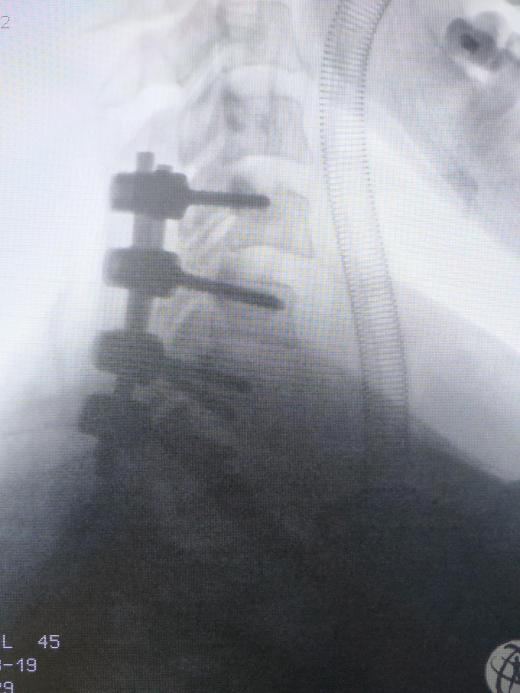

脊柱外科值班醫師接診病人後(hòu)診斷羅阿姨是頸椎骨折脫位并脊髓損傷,合并四肢癱,随後(hòu)醫師爲患者行顱骨牽引治療。針對(duì)羅阿姨的情況,脊柱外科團隊進(jìn)行讨論後(hòu)一緻認爲患者目前四肢肌力0級,胸骨角平面(miàn)以下感覺喪失,鑒于脊髓損傷恢複難度大,卧床并發(fā)症多,最佳治療措施是行頸椎骨折脫位切開(kāi)複位椎弓根螺釘内固定+椎闆切除椎管擴大減壓術。

經(jīng)脊柱外科醫護團隊精心的圍術期準備,在麻醉科的密切配合下,羅阿姨的手術得以順利實施。術後(hòu)第二天,羅阿姨脊髓損傷症狀有較明顯好(hǎo)轉,雙上肢已可擡離床面(miàn),肌力4級,感覺障礙平面(miàn)下降至劍突水平。預計在後(hòu)續的康複治療中,及時(shí)有效的手術減壓固定能(néng)爲患者提供更好(hǎo)的頸椎穩定性,挽救更多的脊髓組織,最大程度的恢複脊髓神經(jīng)功能(néng)。

脊柱外科負責人李建軍表示,頸椎椎弓根釘棒内固定術是頸椎骨折脫位治療中技術難度最大、手術風險最高的手術之一。頸椎解剖複雜精細,其椎弓根直徑最窄處僅爲3mm。頸椎椎弓根内側有頸髓向(xiàng)下走行,椎弓根外側椎動脈穿過(guò),因此其置釘難度非常大。手術中必須保證椎弓根螺釘置釘精準,突破外側皮質可導緻椎動脈和神經(jīng)根損傷,突破内側皮質可侵入椎管,造成(chéng)脊髓損傷,極其考驗手術團隊的技術能(néng)力。